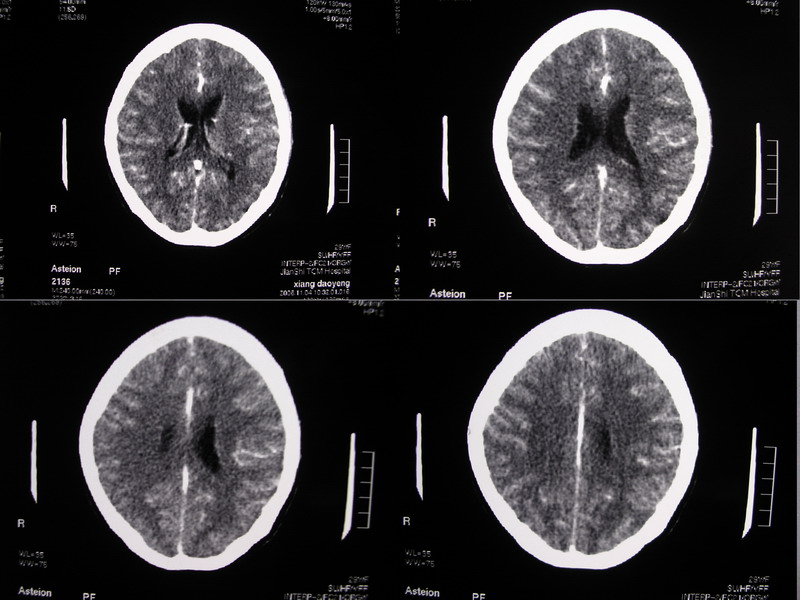

标题: CT5147:头颅,请大家看看

向××,女,29岁,二十天前高热,抗炎治疗后双眼斜视,肌无力,双下肢张力ii级。

除侧脑室额角轻度扩大外,余未见异常。

感觉胼胝体有异常,但看不出异常影像特征,建议行mri进一步确诊.

侧脑室稍扩大,余未见确切异常强化征,请结合脑脊液及脑脊髓mri检查

侧脑室稍扩大,余未见明显异常强化征。

双侧脑室有轻度扩大,增强看脑沟裂显示还是模糊的.时间较长应该考虑脑膜炎.